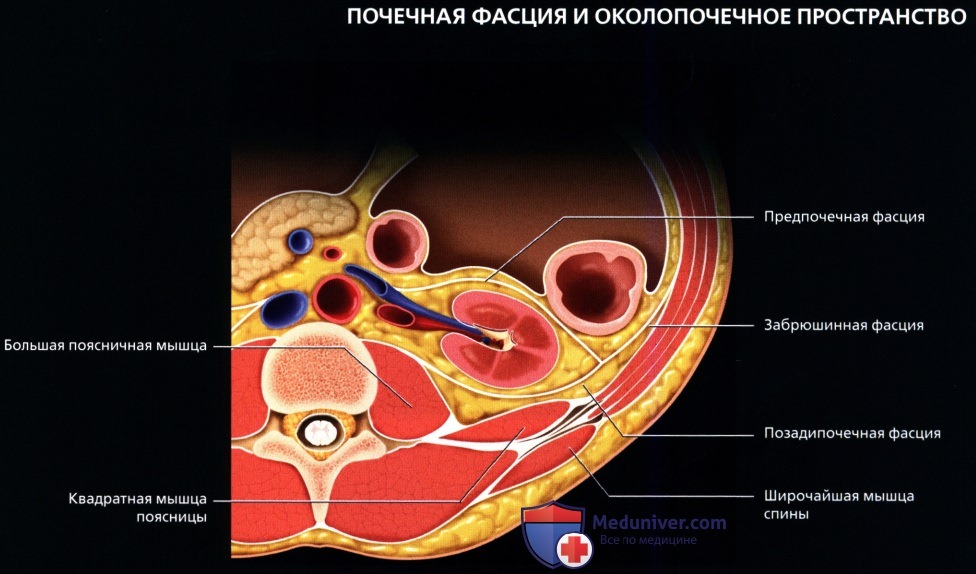

а) Анатомия почек:

2. Топографическая анатомия почки:

• Лежат в забрюшинном пространстве, окружены почечной фасцией (фасция Героты)

• У взрослого каждая почка около 9-14 см в длину и 5 см в ширину

• Обе почки лежат «на» квадратных мышцах поясницы, латеральнее поясничных мышц